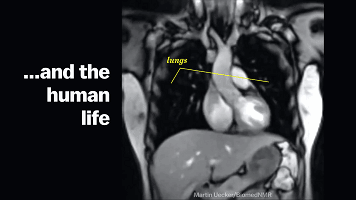

呼吸系统

这里排除体力和激烈运动的原因

我们会发现,在“开啪”之前我们的呼吸就

开始变得有那么一点急促,但这个时候我们

还是可以自我调节控制呼吸节奏来调整状态

这是由于中枢神经的兴奋,使你的血压开始

升高、肌肉收缩、身体代谢也增快,这

直接导致了氧气的加速消耗,所以氧气

摄入会需要提高,从而导致了你呼吸急促